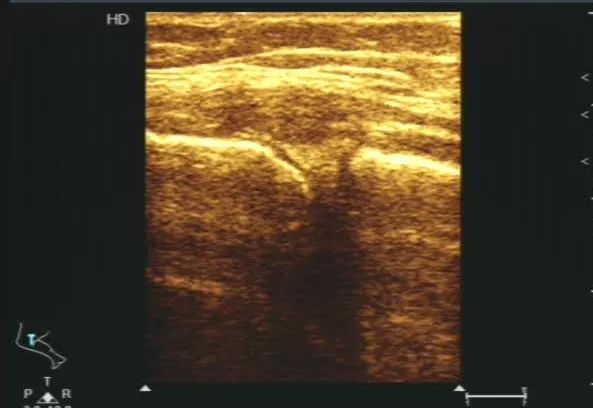

44岁女性患者,右膝关节疼痛,放射检查未见骨关节异常,后来经过肌骨超声检查提示考虑右侧膝关节内侧副韧带挫伤,肌骨超声看到你不知道的肌肉损伤。